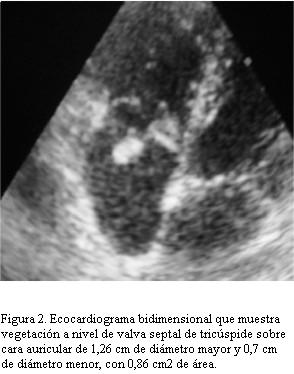

Ecocardiograma: a nivel de valva septal de tricúspide imagen sobre cara auricular de 1,26 cm de diámetro mayor y 0,7 cm de diámetro menor; con 0,86 cm2 de área, móvil, compatible con vegetación endocárdica que genera insuficiencia valvular leve (figura 2). Con diagnóstico de EI sobre válvula tricúspide complicada con derrame pleural secundario a embolia pulmonar séptica se inicia triple plan antibiótico con vancomicina + amikacina + penicilina, hasta el día 3 cuando se obtienen los resultados de los hemocultivos seriados (uno cada 24 h): Staphylococcus aureus meticilino sensible en tres muestras. Posteriormente se ajusta antibioticoterapia según sensibilidad iniciando cefuroxime 150 mg/kg/día. A los 10 días de tratamiento persiste febril (hasta 39ºC axilar) presentando dolor tipo puntada de lado y síndrome en menos en tercio inferior de hemitórax derecho que se interpreta como reiteración de embolia pulmonar séptica. Los hemocultivos obtenidos a los 5 y 6 días de evolución en CI persistían positivos para Staphylococcus aureus meticilino sensible.

- 1-10 días de tratamiento: vegetación móvil pedunculada de 1,53 cm de diámetro mayor y 0,72 cm de diámetro menor sobre cara auricular de valva septal tricúspide, con implantación firme de amplia motilidad.

- 2-17 días de tratamiento: vegetación de 1,47 cm de diámetro mayor y 0,82 cm de diámetro menor, área de 0,85 cm2, pedunculada de amplia movilidad que se desplaza desde aurícula derecha a ventrículo derecho con engrosamiento de valva septal, genera insuficiencia valvular leve. Sin masas intracavitarias libres.

De acuerdo a los criterios modificados de Duke nuestro caso se trataba de una EI definida dado que cumplía dos criterios mayores (8): 1) hemocultivo positivo para un microorganismo típico (Staphylococcus aureus) en dos muestras separadas; 2) ecocardiograma positivo: masa intracardíaca oscilante sobre valva.

El caso descrito requirió de tratamiento quirúrgico en la fase activa de la enfermedad (menos de 6 semanas de tratamiento antibiótico apropiado completadas) (11). La indicación de cirugía estaba dada por la reiteración del episodio de embolia pulmonar y presentar una vegetación con alto grado de movilidad de gran tamaño que no disminuyó el mismo a pesar del tratamiento, características éstas que son altamente sugestivas de la posibilidad de nuevos eventos embólicos con mayor compromiso pulmonar. Di Salvo, en un estudio en adultos en el cual define a la EI con los criterios de Duke (usando ecocardiografía transesofágica), establece una correlación entre el tamaño y la movilidad de la vegetación y las posibilidades de eventos embólicos, obteniendo como resultado que con vegetaciones menores de 10 mm, de 10 a 15 mm y mayores de 15 mm, la frecuencia respectiva de eventos embólicos es del 26%, 42% y 70%. Para clasificar la movilidad de las vegetaciones se consideran las siguientes características: ausente, es sinónimo de movimiento no detectable; bajo, vegetación con base fija pero con borde libre móvil; moderado, vegetación pedunculada que se mantiene dentro de la misma cámara en el transcurso del ciclo cardíaco; severo, cuando existe una vegetación prolapsante que cruza el plano de coaptación de las valvas durante el ciclo cardíaco. Los eventos embólicos se presentaron con una frecuencia del 17%, 35% y 81% para bajos, moderados o altos grados de movilidad respectivamente (12). El hecho de que el trabajo de Di Salvo se basa en estudios ecocardiográficos transesofágicos no invalida la aplicación de sus resultados en niños dado que la ecocardiografía transtorácica es más sensible en la población pediátrica que en adultos para detectar y valorar vegetaciones, sobre todo cuando el paciente no presenta anomalías estructurales cardíacas (1,5).